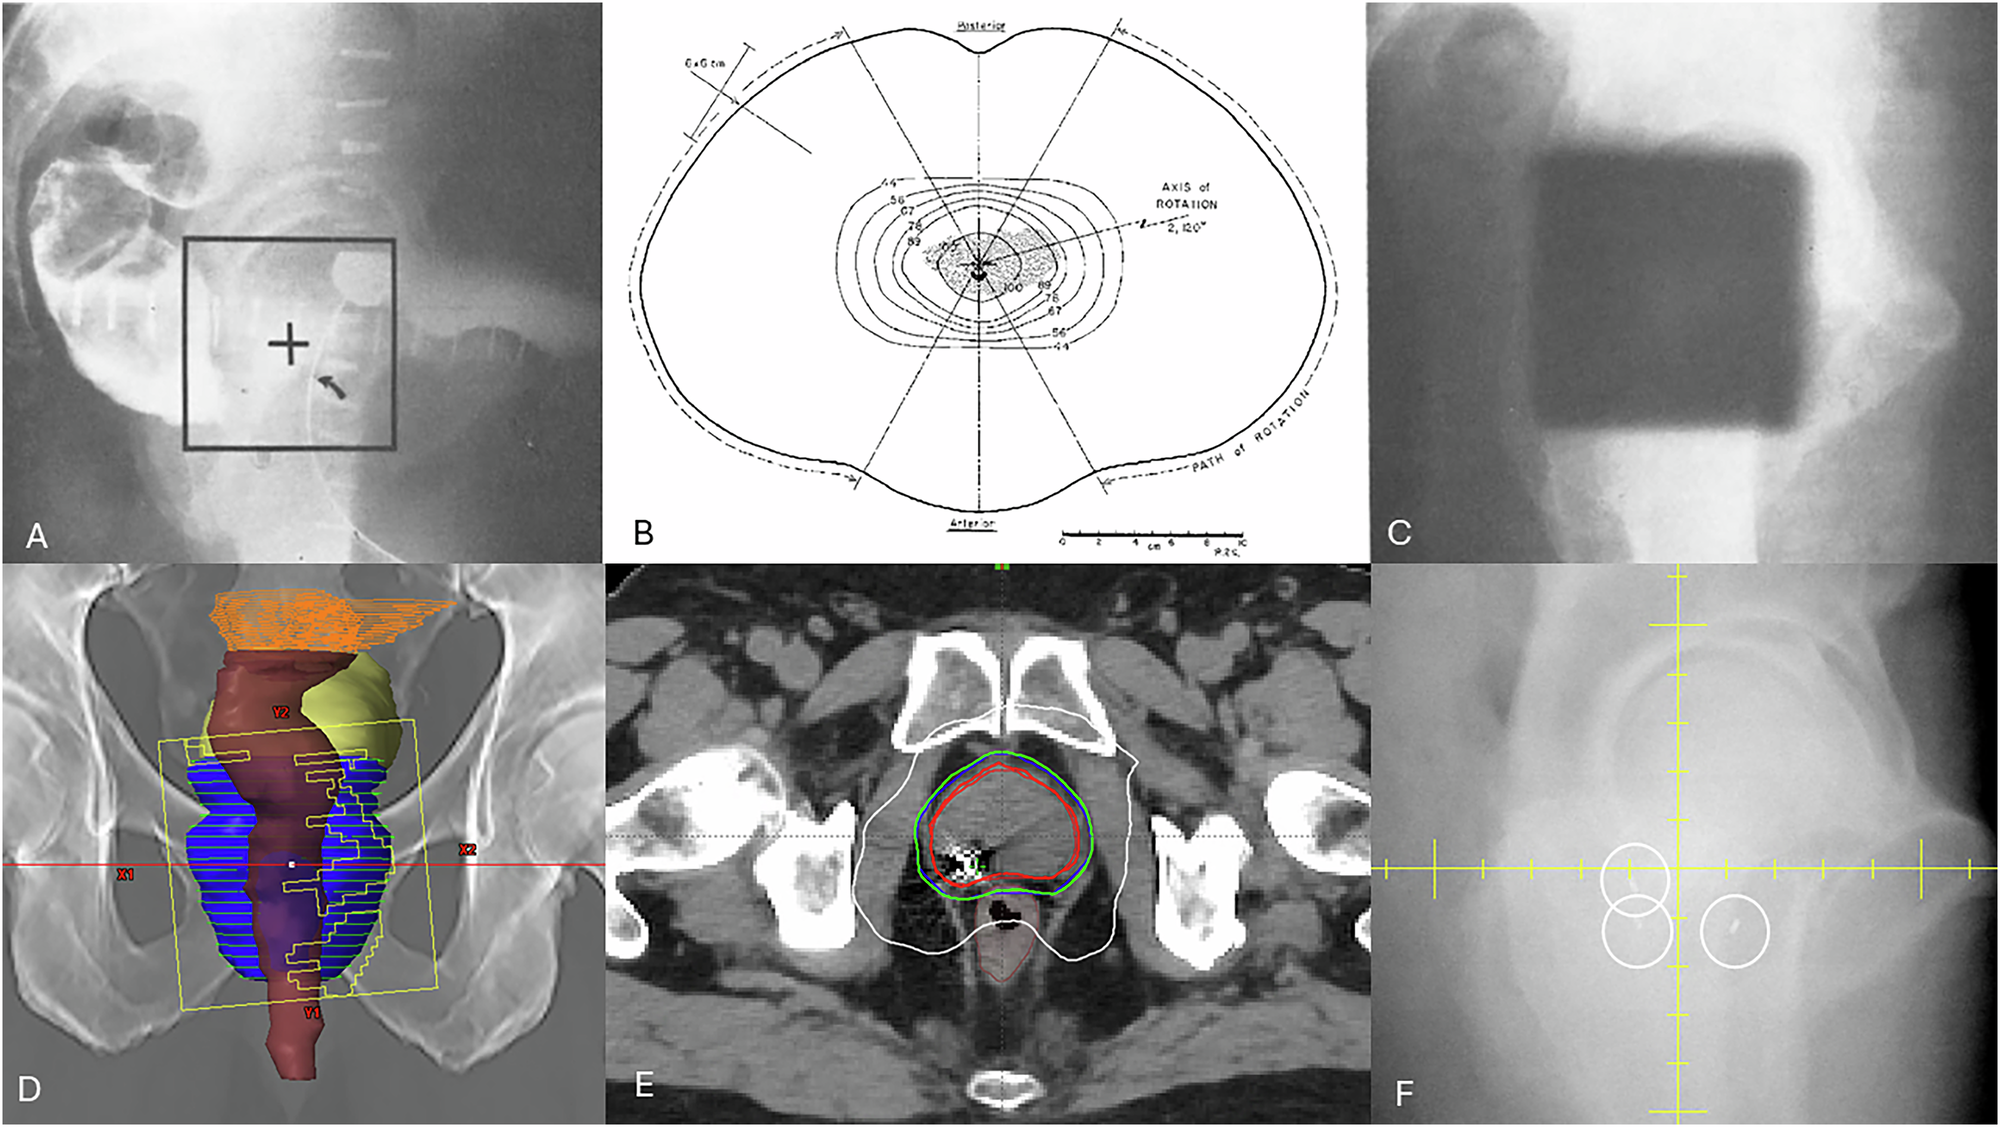

Fig. 1: Prostate cancer treatment then and now.

A Kilovoltage lateral simulator image used to set isocentre and field borders (square) based on inferential information of the prostate based on surrounding anatomy (rectal and bladder contrast, foley balloon, bony pelvis) B rotational therapy that creates an in-plane conformal delivery but lack of dynamic beams eye view shaping limits the ability to conform the beam to the actual prostate shape; such rotational delivery allowed the treatment of deep seated tumors with lower energy (1–4MV) x-rays C) image guidance using “port film” acquired by exposing an x-ray film prior to treatment showing alignment of the treatment beam (dark square) in relation to bony anatomy. D Digitally reconstructed radiograph of anterior view of pelvis reconstructed from CT imaging with superimposed contours for prostate (blue) rectum (brown) bladder (yellow) and MLC aperture design at start of a dynamic, intensity modulated arc (note the aperture is only treating part of the prostate) E conformal dose distribution from the volumetric dynamic arc therapy also demonstrating a fiducial marker used for image guidance F on board imaging used for dynamic tracking of the implanted fiducial marker during treatment.